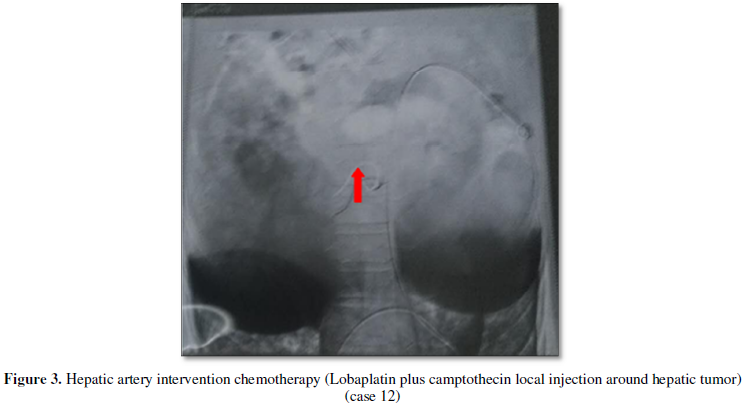

Case 12: A 41 year old man stated that he was disgusted with taste of greasy, accompanied with nausea and vomiting for one month, and chief complaint of abdominal mass one day ago. At physical examination showed 6 × 5 cm harden mass in his hepatic lesion, and an enlarged liver was felt 7 cm below the right costal margin. Laboratory data included serum AFP 40.59 ng/ml (control 0-7 ng/ml), CEA 5.86 (control<5.0 mg/L), CA-125 63.0 (control<35.0 u/ml), CA-159 91.31 (control<35.0 ku/L), serum HBsAg (-), serum HBsAb 53.3 (+), serum HBeAg (-), serum HBeAb 1.29 (+), serum HBcAb 1.45 (+). He was diagnosed as advanced HCC. Treatment consisted of hepatic artery intervention chemotherapy (Lobaplatin plus camptothecin injection, Figure 3) in another provincial tumor hospital and demethylcantharidin tablets. He was in stable disease for 3 months and now being treated in other hospital.